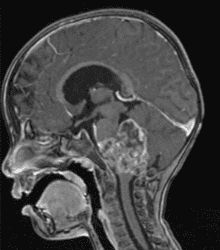

毛様細胞性星細胞腫 | 上衣腫 | 髄芽腫 | 脳幹部腫瘍 |

胚細胞性腫瘍 | 脈絡叢乳頭腫 | 頭蓋咽頭腫 | その他の小児脳腫瘍 |